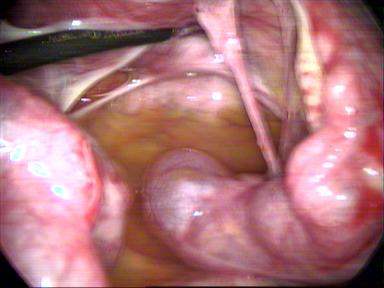

PCOD Drilling

During operative laparoscopy, many abdominal disorders can be treated safely through the laparoscope at the same time that the diagnosis is made. When performing operative laparoscopy, the physician inserts additional instruments such as probes, scissors, grasping instruments, biopsy forceps, electrosurgical or laser instruments, and suture materials through two or three additional incisions. Lasers, while a significant help in certain operations, are expensive and are not necessarily better or more effective than other surgical techniques used during operative laparoscopy. The choice of technique and instruments depends on many factors including the physician’s experience, location of the problem, and availability of equipment. Some problems that can be corrected with operative laparoscopy include removing adhesions (scar tissue)from around the fallopian tubes and ovaries, opening blocked tubes, removing ovarian cysts, and treating ectopic pregnancy. Endometriosis can also be removed or ablated from the outside of the uterus, ovaries or peritoneum. Under certain circumstances, fibroids on the uterus can also be removed. Operative laparoscopy can also be used to remove diseased ovaries and can be performed as part of a hysterectomy.